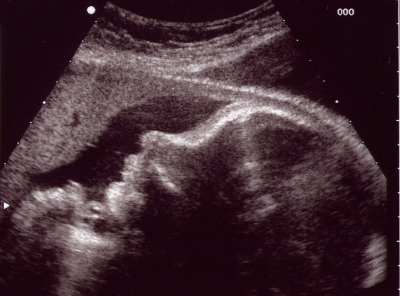

voila l'écho est faite bébé se porte bien et je suis rassurée sur le poid il pèse environ 3k100g pour le moment donc c pas un gros bébé oufff  le gynéco a dit que ce serai bien si j'accouché la semaine prochaine mais bon c pas moi qui decide lol

et oui aujourd'hui 9h00 derniere écho de la 39eme semaine je vois le bout plus que 14 jours on se languis (surtout moi car je dors plus lol) a tout a l'heure pour une autre foto peut etre bisous